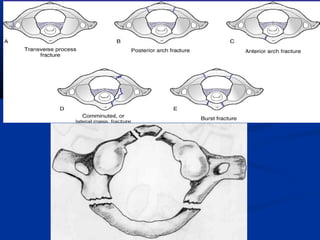

�# OF ATLAS:

�Posterior arch #: 2/3rdof all #, occur at the junction of

posterior arch & lateral mass (hyperextension injury).

�Anterior arch #: rare

�Jefferson s # : burst # of atlas,

1st

described by Geoffrey jefferson in 1920.

Axial loading –downward displacement of condyles with

separation of lateral mass of C1.

Classically 4 part # -2 # each in ant & post arch.

neck pain & stiffness

Cervical collar / Halo immobilization

Non union –occiputto C2 fusion

open-mouth show lateral spine

dispalcement of lateral masses of C1

CT scan of C1 shows fratures

through anterior and

posterior rings of C1